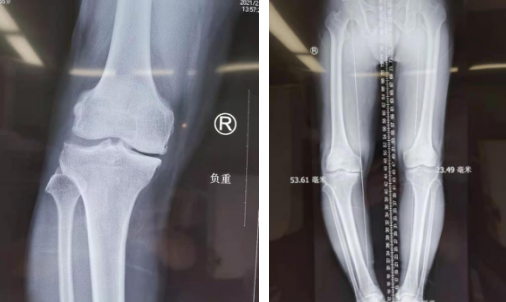

听从儿女建议,万大姐来到仁慈医院关节科就诊,门诊医生询问病史、查体,万大姐右下肢内翻畸形,右膝关节肿胀,右下肢比左下肢短约2厘米;结合影像检查,诊断为:右膝关节骨性关节炎,右膝关节半月板损伤,右膝关节游离体。

术前

张传开主任团队评估万大姐的膝关节炎为中度,万大姐年纪还不大,应首选保膝治疗。这是一种既能纠正畸形减轻疼痛,又可保留患者自然的膝关节,最大程度地保留关节的运动功能和舒适性的一种治疗方案。团队讨论后,决定采用关节镜探查、机器人精准定位截骨,微创完成这起保膝手术。

第二天,张传开主任郝亮闫成尚医生团队为患者进行了关节镜探查+机器人辅助下胫骨截骨术。术中,医生镜下探查,可见右膝关节滑膜充血水肿变性,内侧半月板撕裂严重,右股骨内髁软骨剥脱,针对镜下探查情况,予以病变半月板清除,剥脱软骨清理及滑膜切除术。随后,在骨科机器人的精准定位下进行截骨,很大程度减少软组织和骨组织的损伤,患者出血少、创伤小,术后膝关节功能的康复将更快,患者感受也会更好。